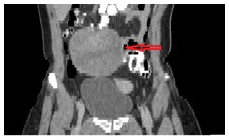

The CT (Figures 2–4) showed a large, multi-spaced, clearly defined circumscribed mass composed of cystic and solid components with a volume of 400milliliters (maximum diameter: 10.8cm).The mass extended up to the level of the right distal ureter without infiltrating it. Normal lymph nodes (para-aortic space) were noted. No other pathological findings were detected in the abdomen.

Figure 3 CT abdomen (coronal plane) shows the cyst presence in the right ovary (10,5 cm×7cm sizes) with solid and cystic elements. The red arrow indicates the lesion.